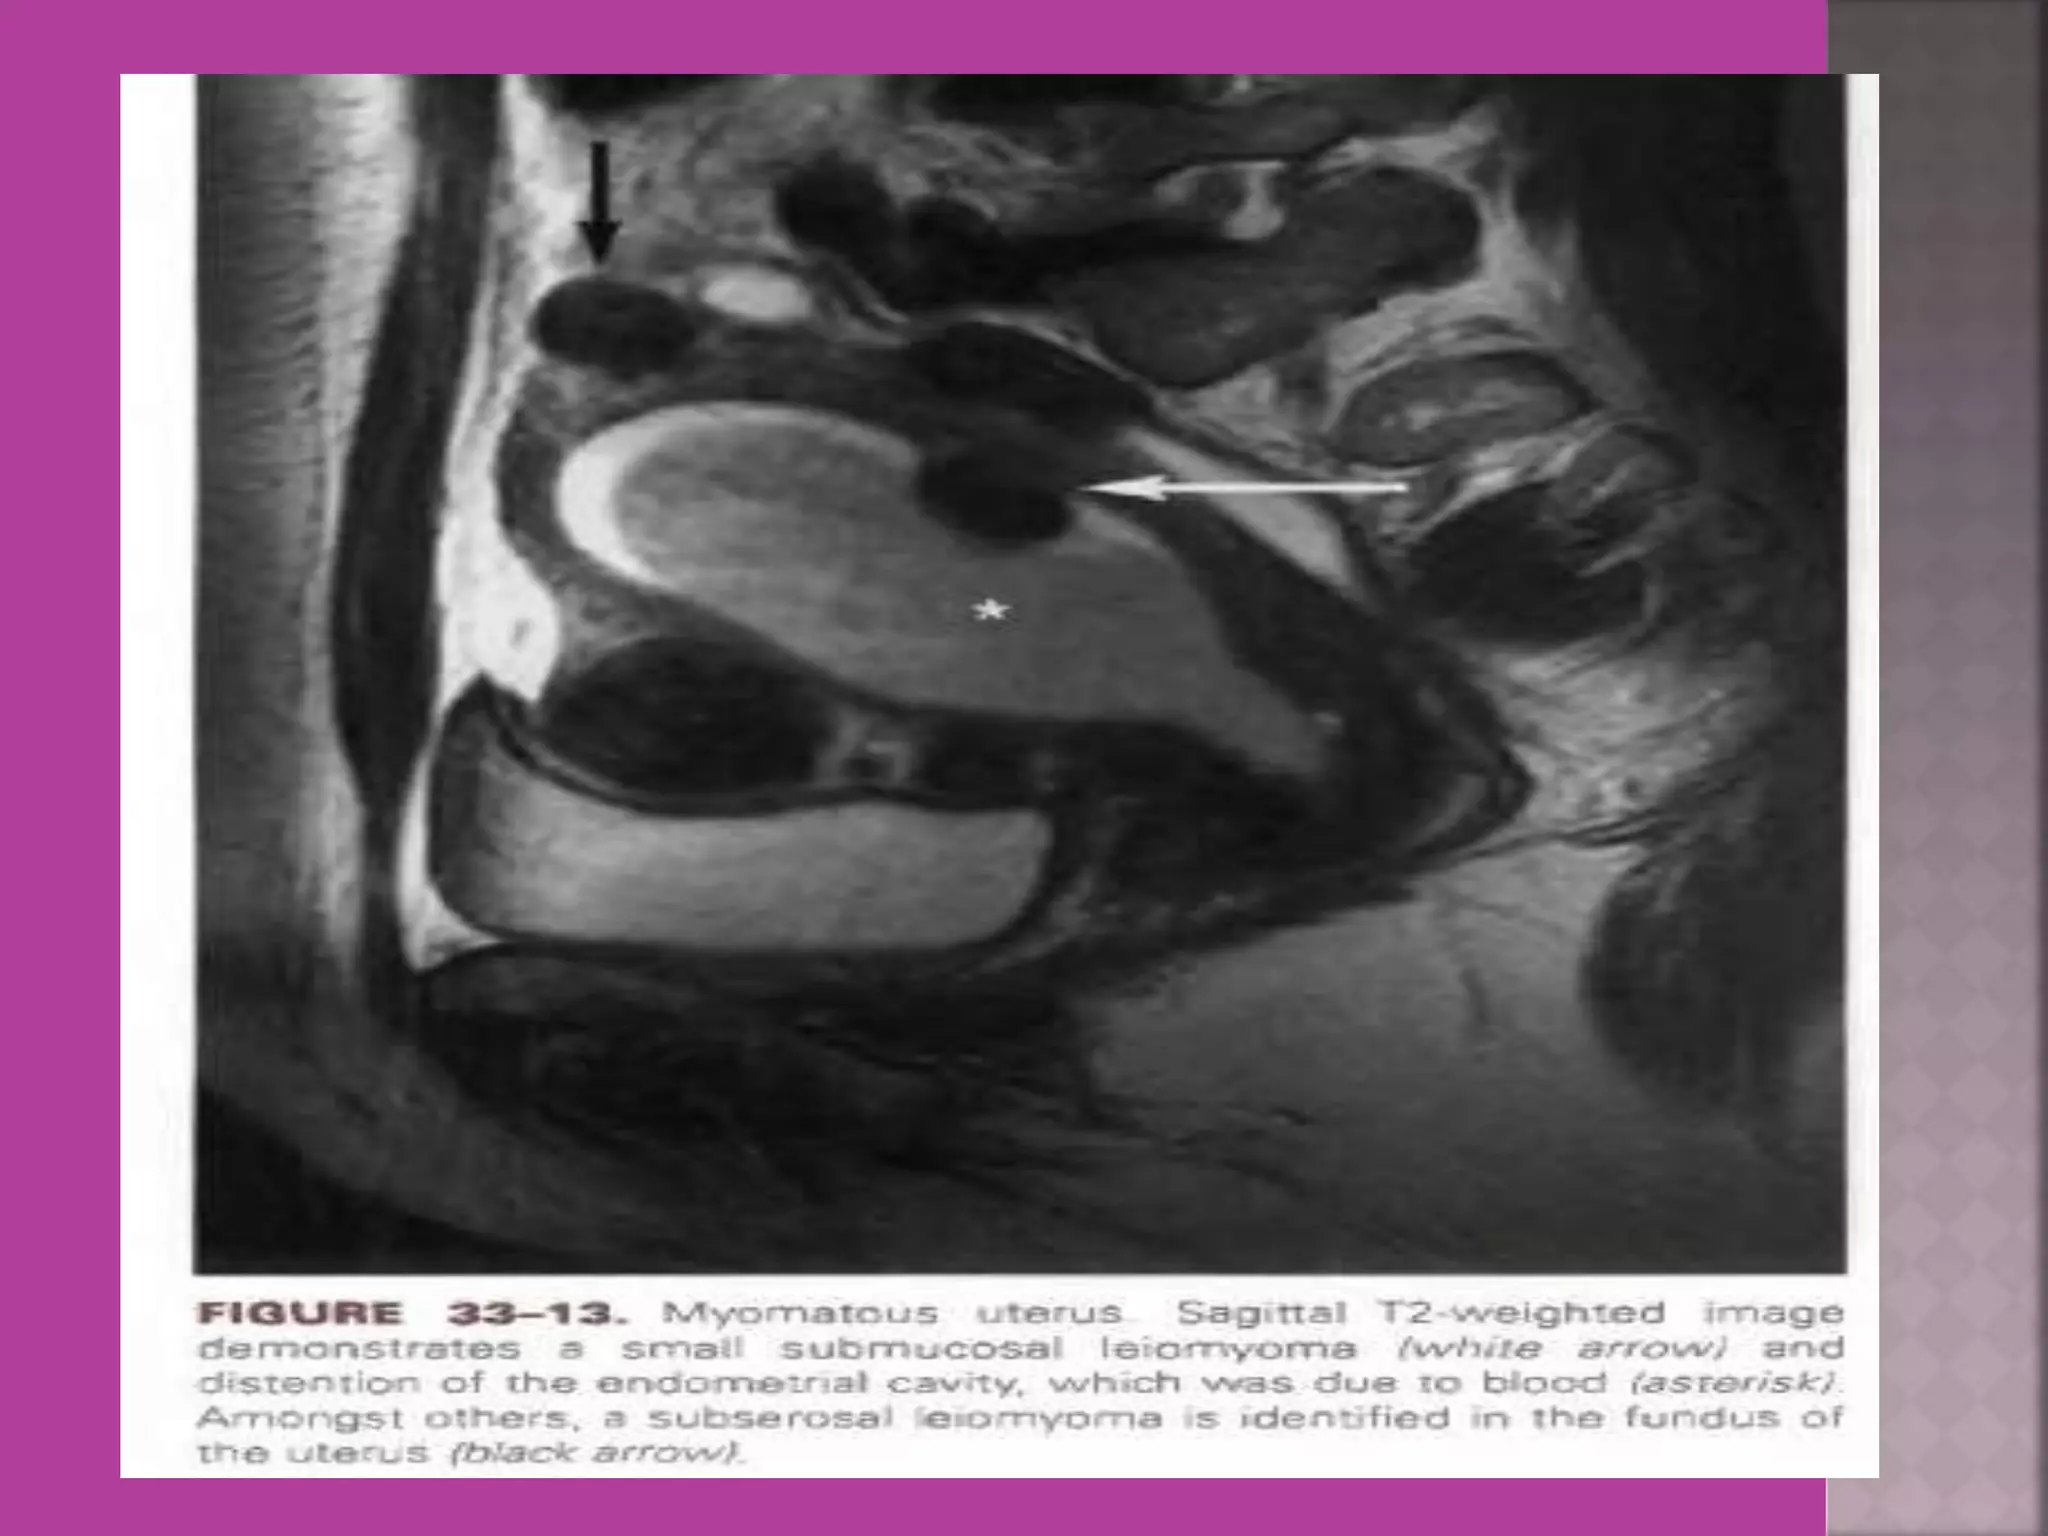

 Myoma—to differentiate myoma from

adenomyoma.localization of myoma—sub

serous/ intra mural or sub mucous.

Degeneration Of Fibroid

Cystic Degeneration of

Fibroid

 Study ofnormal uterus and adnexa – with aim to have clear image of normal myometrium, endometrium , ovary and follicles within the ovary.  Myoma—to differentiate myoma from adenomyoma.localization of myoma—sub serous/ intra mural or sub mucous.  Adenomyosis---accurate diagnosis.  Congenital uterovaginal anomalies— bicornuate, septate,subseptate , unicornuate, didelphys ,rudimentary horn and vaginal atrasia etc